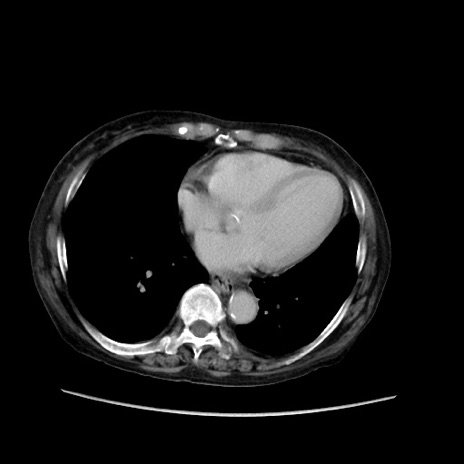

症例31(横断像)

【症例】80歳代 女性

【主訴】腹部膨満感

【現病歴】他院にて肝硬変にてフォロー中。1週間前から便秘、腹部膨満感、臍部腫瘤あり受診となる。

【既往歴】肝硬変

【身体所見】腹部膨隆あり、皮膚変化なし、疼痛なし。

【データ】WBC 4600、CRP 0.25